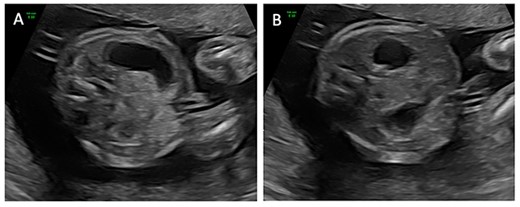

A 24-year-old G2P0010 woman was referred to our fetal care center at 21- and 2/7-weeks’ gestation following routine ultrasound that identified ascites, dilated small intestine and absent versus right-sided stomach. Fetal ultrasound performed at our institution demonstrated a dilated stomach with possible ‘double-bubble’ sign (Fig. 1). Fetal magnetic resonance imaging (MRI) confirmed dilation of the stomach and proximal duodenum without clear distinction between the two structures (Fig. 2), suspicious for duodenal atresia. Polyhydramnios was not seen on either ultrasound or MRI. She was scheduled for amniotic fluid index (AFI) evaluations (Table 1) and biophysical profiles (BPP) every 2 weeks with monthly growth ultrasounds, and induction was planned at 39-weeks’ gestation. At 30- and 2/7-weeks’ gestation, her AFI was mildly elevated at 29.7 cm (normal 5–25 cm). The ‘double-bubble’ sign was not identifiable on any follow-up evaluation. At 34- and 5/7-weeks’ gestation, she presented with decreased fetal movement. Her BPP was abnormal with absent fetal breathing episodes and a non-reactive non-stress test, necessitating further surveillance and ultimately Cesarean section. The infant was initially apneic, cyanotic without grimace and bradycardic. There was no response to continuous positive airway pressure ventilation requiring intubation with improvement in hemodynamic status. Oro-gastric sump tube placement was attempted but could not be advanced past the proximal esophagus. Radiographs noted coiling of the sump tube within the proximal esophagus and a gasless abdomen. On day of life two, the infant was taken to the operating room for rigid bronchoscopy and laparoscopic gastrostomy tube placement. Bronchoscopy demonstrated normal tracheal and bronchial anatomy. The bronchoscope was used to evaluate the esophagus and confirmed a blind-ending esophageal pouch. A gastrostomy tube was placed laparoscopically without issue but upon insufflation of the stomach, froth was noted along the lesser curve just proximal to the pylorus. A supra-umbilical midline incision was made to further evaluate, and a gastric perforation was noted. A red rubber catheter was passed through the perforation and met obstruction within the second portion of the duodenum. The perforation was repaired, and a standard duodenoduodenostomy was performed.

Transverse ultrasound images obtained at 21- and 2/7-weeks’ gestation demonstrating a dilated stomach (A) with possible ‘double-bubble’ sign (B).